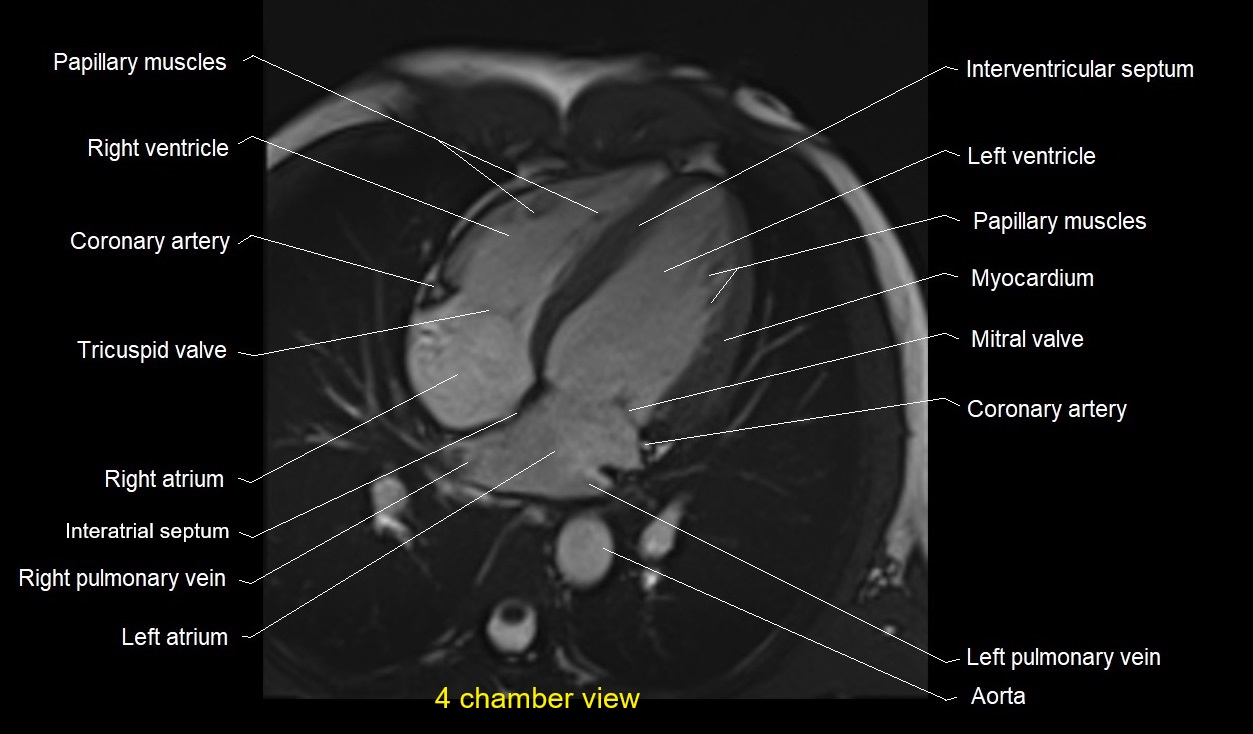

MRI image